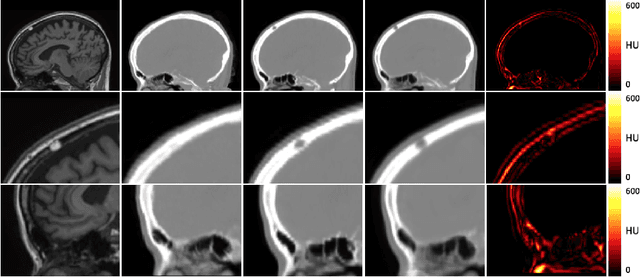

Abstract:Attenuation correction is an essential requirement of positron emission tomography (PET) image reconstruction to allow for accurate quantification. However, attenuation correction is particularly challenging for PET-MRI as neither PET nor magnetic resonance imaging (MRI) can directly image tissue attenuation properties. MRI-based computed tomography (CT) synthesis has been proposed as an alternative to physics based and segmentation-based approaches that assign a population-based tissue density value in order to generate an attenuation map. We propose a novel deep fully convolutional neural network that generates synthetic CTs in a recursive manner by gradually reducing the residuals of the previous network, increasing the overall accuracy and generalisability, while keeping the number of trainable parameters within reasonable limits. The model is trained on a database of 20 pre-acquired MRI/CT pairs and a four-fold random bootstrapped validation with a 80:20 split is performed. Quantitative results show that the proposed framework outperforms a state-of-the-art atlas-based approach decreasing the Mean Absolute Error (MAE) from 131HU to 68HU for the synthetic CTs and reducing the PET reconstruction error from 14.3% to 7.2%.